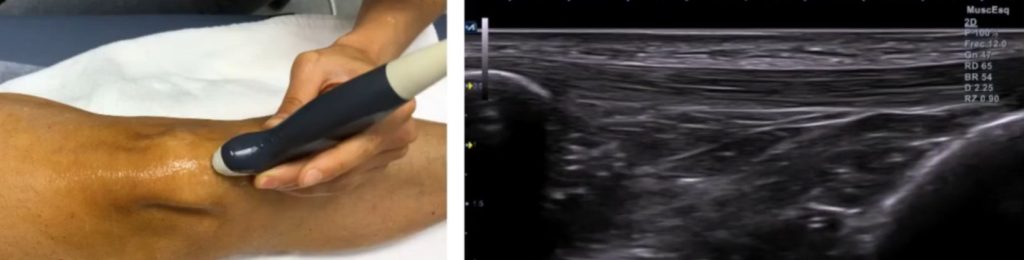

Cómo explorar el tendón rotuliano con ecografía

El corte de referencia longitudinal, incluirá las corticales de la tuberosidad tibial anterior y el polo inferior de la rótula.

Cuando más lateral o medial se haga el corte, más fino será el tendón.

Una vez exploradas las estructuras en longitudinal, pasaremos a un corte transversal.

En este corte deberás hacer un barrido de craneal a caudal para explorar el tendón en toda su longitud.